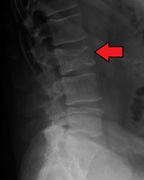

Pathological fracture of the lumbar spine due to multiple myeloma